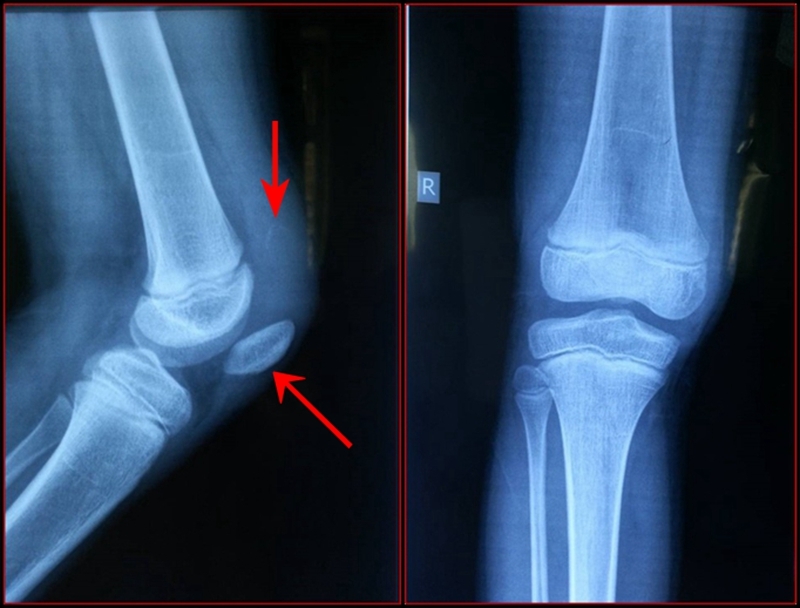

图1 受伤当时X线片

图2 受伤3周X线片